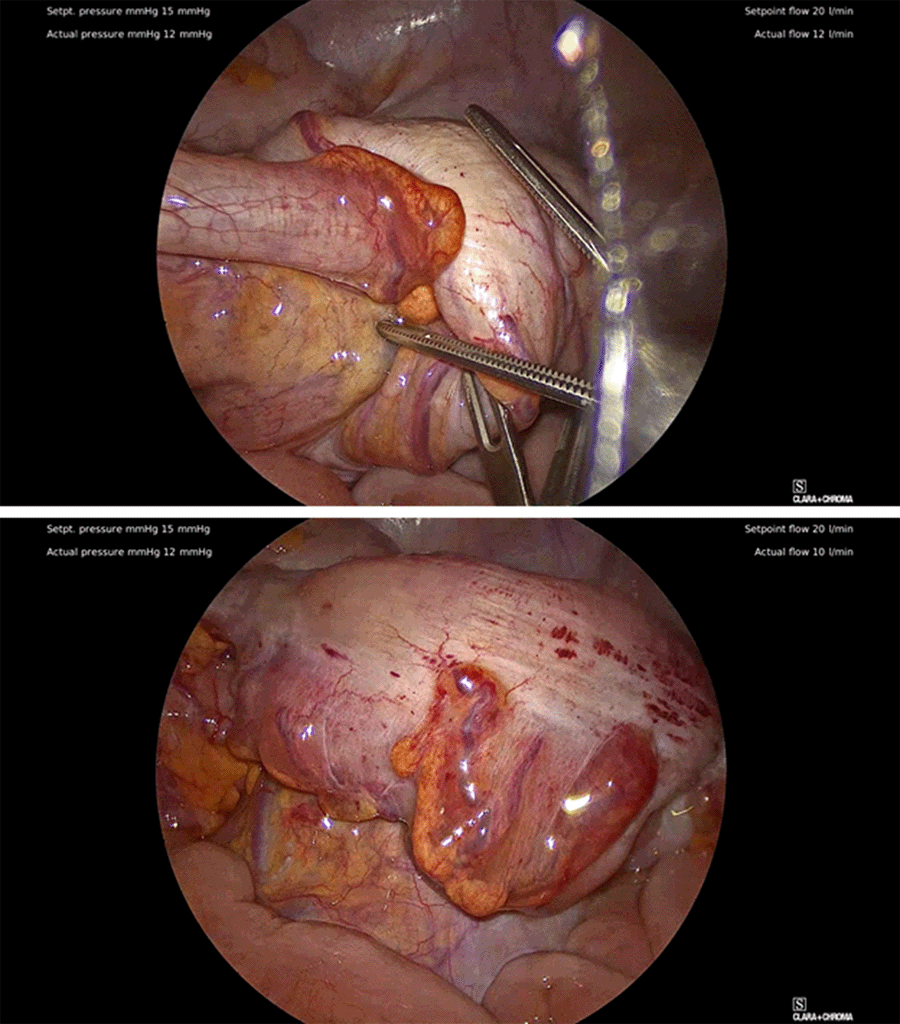

Figure 4. Identification of Rectosigmoid Intussusception. Published With Permission

Rectosigmoid intussusception was seen intraoperatively (top) and reduced without significant resistance (bottom). No signs of bowel necrosis or perforation.